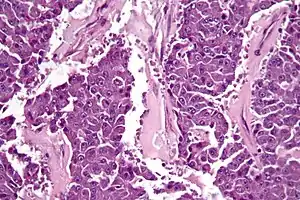

Carcinoma de células acinares do pâncreas

Carcinoma de células acinares do pâncreas é um tumor pancreático exócrino raro e maligno. Corresponde a 5% de todos os tumores do pâncreas, sendo o segundo tipo mais comum de cancro do pâncreas.[1]